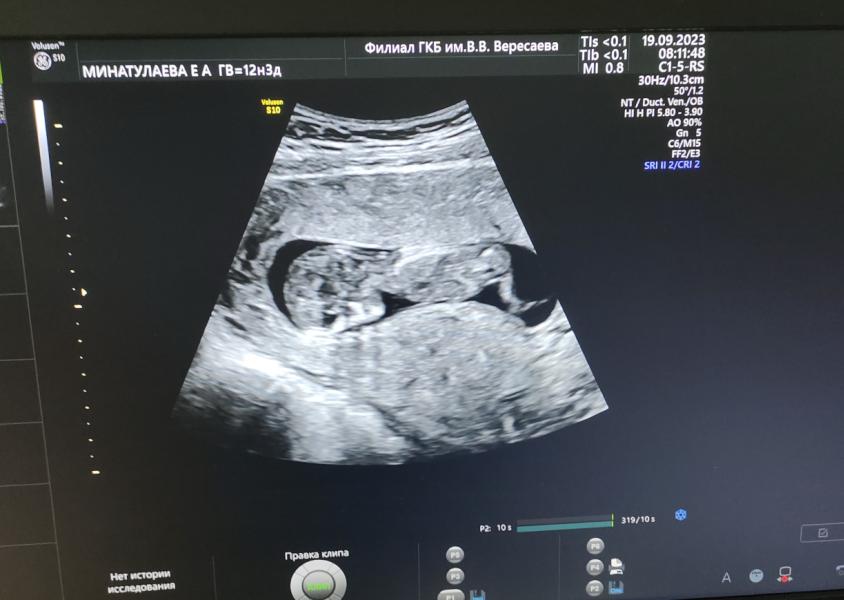

Прошли первый скрининг, по УЗИ все хорошо, кровь думаю тоже будет норм, результат 27.09, пол не предположили, поэтому придется ждать еще месяц и идти на УЗИ 🥰